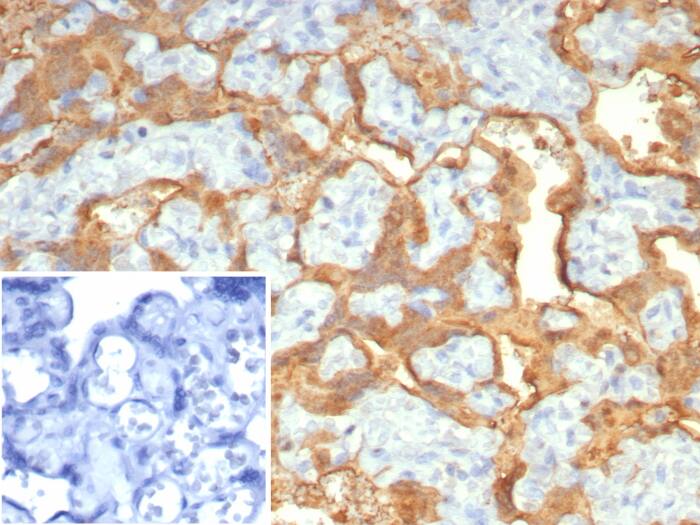

Formalin-fixed, paraffin-embedded human placenta stained with S100P Recombinant Mouse Monoclonal Antibody (S100P/7373). Inset: PBS instead of primary antibody; secondary only negative control.Applications for S100P Antibody (S100P/7373)